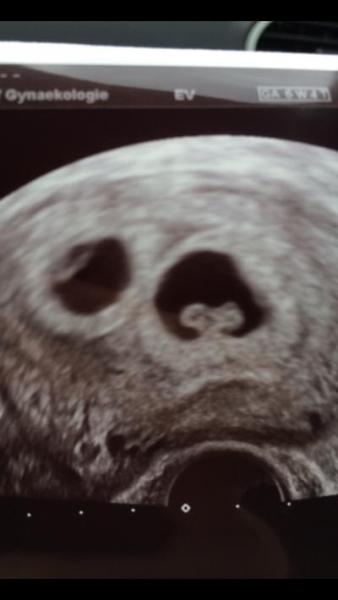

Wollte euch mal Mut machen!!! Bin jetzt in der 7. SSW und mit Zwillingen Schwanger!!! 2 Embryos in C und D Qualität wurden eingesetzt und man machte mir nicht viel Mut und siehe da beide haben es sich gemütlich gemacht und das gleich bei der 1. ICSI... Die Herzchen schlagen auch schon :-) Euch alles gute und viel Glück